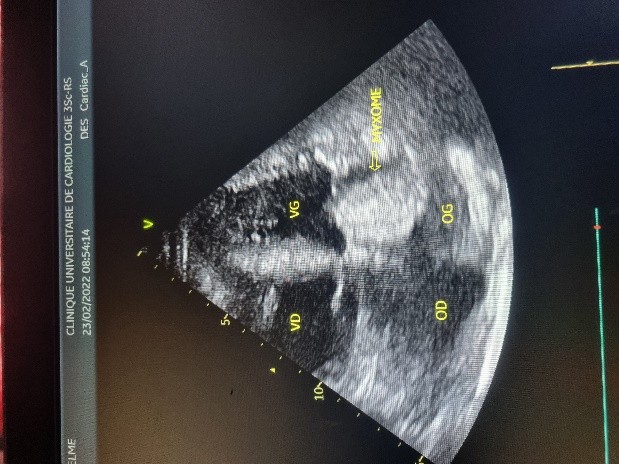

L’électrocardiogramme notait un rythme sinusal régulier avec une fréquence cardiaque à 83 bpm, des anomalies de la repolarisation en antéro septal à type d’ondes T biphasiques et en inférieur à type d’ondes T négatives asymétriques. La biologie était normale. L’échocardiographie (transthoracique et transœsophagienne) retrouvait les mêmes caractéristiques avec une masse appendue à la face atriale de la grande valve mitrale, obstruant partiellement l’orifice mitral et mesurant 49mm ×27 mm. Elle faisait protrusion dans le ventricule gauche en diastole (Figures 5 et 6). Cette masse était évocatrice d’un myxome de l’oreillette gauche. Le ventricule gauche n’était pas dilaté (DTDVG= 46mm), avec une fraction d’éjection systolique à 74% au Simpson biplan. Les pressions de remplissage du ventricule gauche étaient élevées. L’oreillette gauche était dilatée (VOG= 43mL/m²). Les cavités droites n’étaient pas dilatées. La fonction ventriculaire droite était normale (TAPSE= 24mm). On notait une hypertension pulmonaire avec PAPS =75mmHg, VmaxIT= 4,18 m/s. La veine cave inférieure était fine et compliante.

Figure 5 (a, b et c): Echocardiographie transthoracique en mode bi dimensionnel montrant un large myxome de l’oreillette gauche appendu à la face atriale de la grande valve mitrale faisant protrusion dans le ventricule gauche en diastole vu en incidence apicale 4 cavités (a et b) et 2 cavités avec doppler couleur notifiant une insuffisance mitrale (c) chez un patient de 57 ans. (Cas clinique n° 3). VG= ventricule gauche ; OG= oreillette gauche ; OD= oreillette droite ; VD= ventricule droit